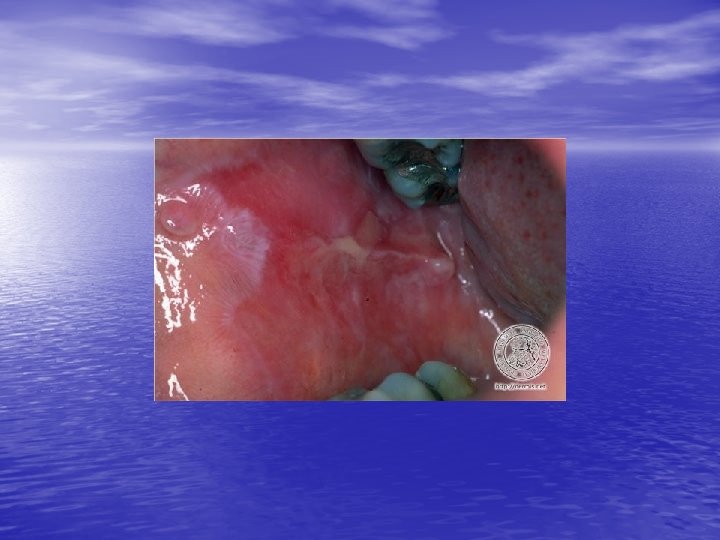

Physical examination • Skin lesions: Violaceous, shiny papules, with white lines ( Wickham’s striae). Polygonal or oval lesions. Grouped, linear ( isomorphic phenomenon), anular or disseminated scattered discrete lesions when generalized. In dark-skinned individuals, post-inflammatory hyperpigmentation is common. • Clinical variants: Hypertrophic, follicular, vesicular, actinicus, ulcerative • Mucous membranes: 40 -60%, reticular, erosive or ulcerative • Genitalia: Papular, annular or erosive • Hair and nails: Scalp (scarring alopecia), nail ( pterygium formation!, longitidunal ridging, splitting, oncholysis, red lunula, idiopathic atrophy of the nails, yellow nail syndrome, twenty-nail dystrophy) • Nail involvement: %5 -10. Especially in children, it can occur as an initial manifestation!

Diagnosis and differential diagnosis • Clinical findings confirmed by histopathology • Papular LP: Psoriasis, p. rosea, chronic cutaneous lupus • • • erythematosus, eczema, lichenoid GVHD. Hypertrophic LP: Psoriasis, lichen simplex chronicus, prurigo noularis, kaposi’s sarcoma. Drug-induced LP: Beta-blockers, antimalarials, thiazide diuretics, furosemide, spironolactone, penicillamine, ACE inhibitors, ca channel blockers, NSAİD’s, sulfonylurea Mucous membranes: leukoplakia, candidiasis, hıvassociated hairy leukoplakia, lupus erythematosus, bite trauma, mucous patches of syphilis, pemfigus vulgaris.